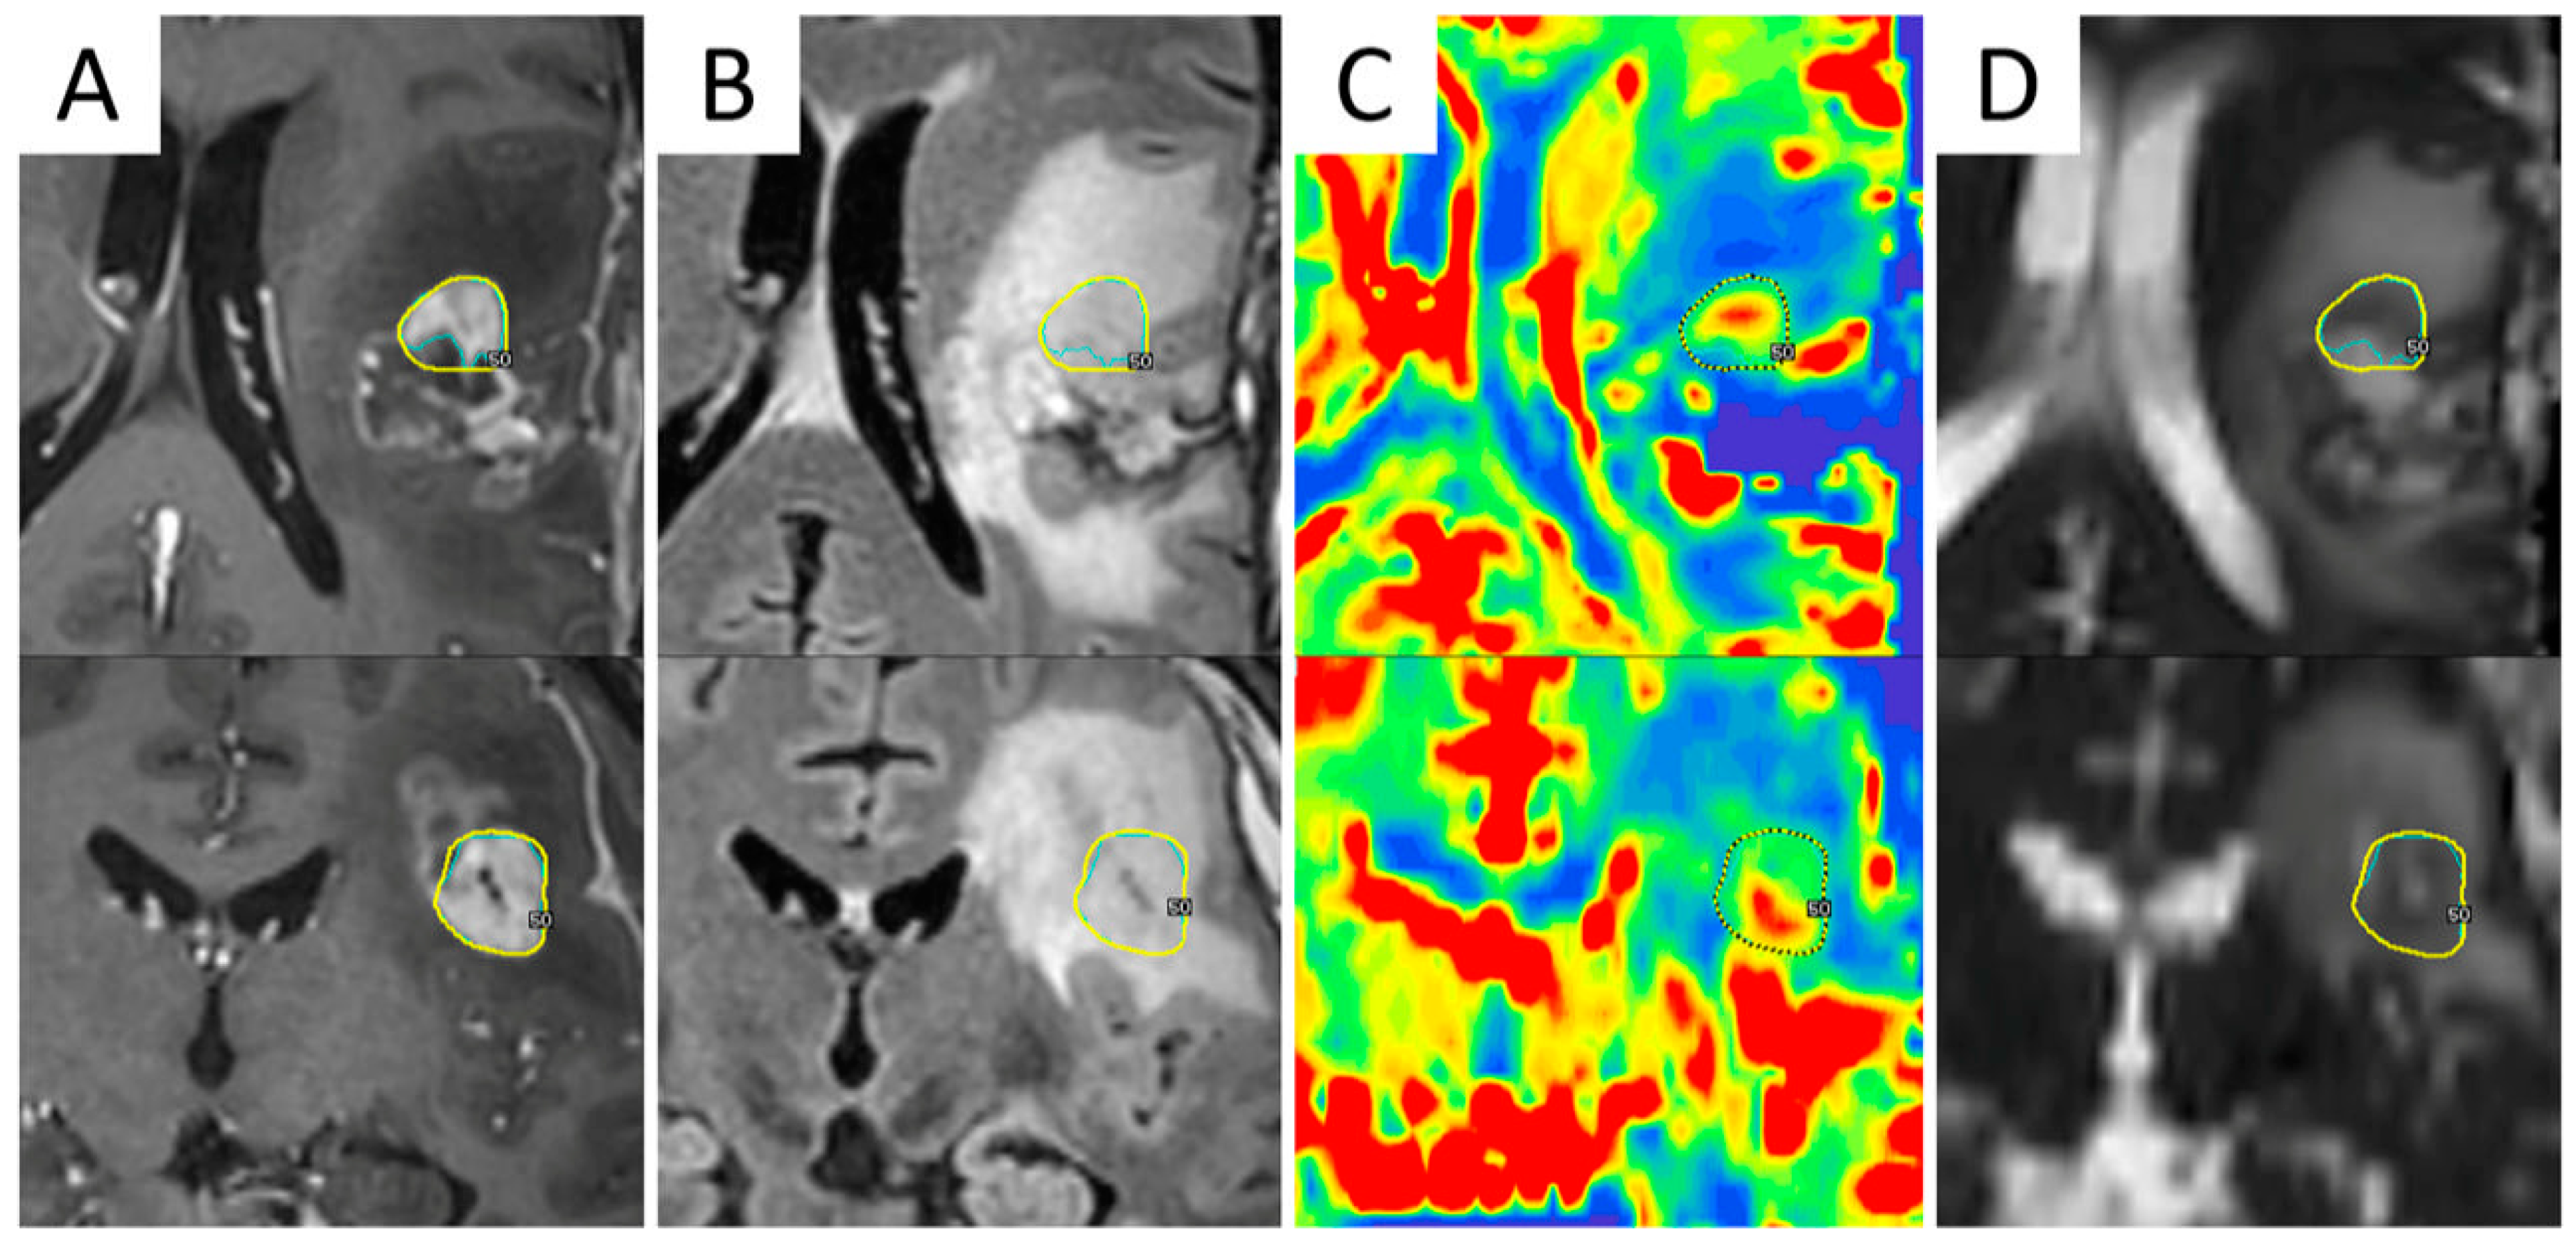

Figure 5.

Integration of F-DOPA PET/CT in a LINAC-based radiosurgical planning of a 55-year-old female patient with recurrent GBM. (A) shows GTV based on contrast-enhanced T1-weighted MRI images; (B) shows remarkable F-DOPA uptake extending beyond contrast-enhancement. The final target volume was delineated by taking into account the F-DOPA-positive signal (C). Three-month follow-up (D) shows tumor progression at the site of pre-RT increased F-DOPA uptake, despite salvage irradiation.